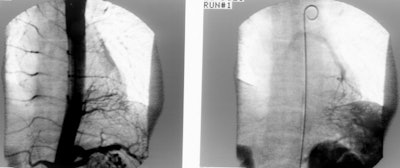

An arteriogram was performed and reveal a systemic arterial supply to the mass with pulmonary venous drainage. The mass was resected and determined to be an intralobar bronchopulmonary sequestration.